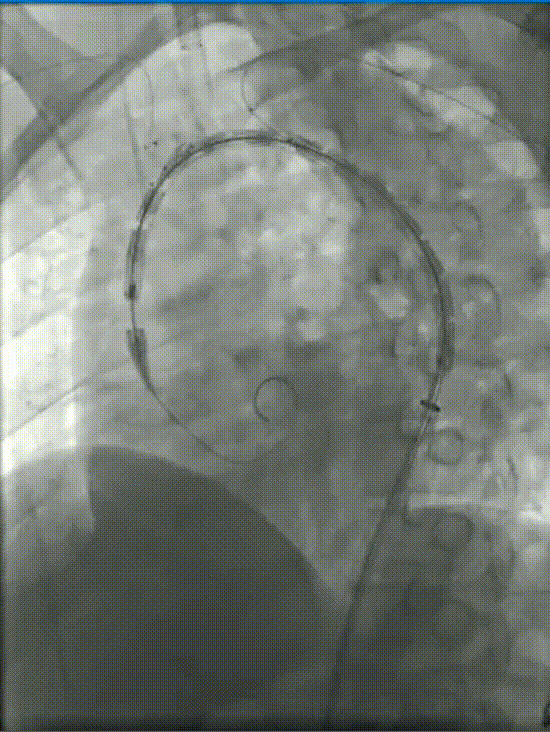

2. 主体支架释放

通过预弯外鞘将主体支架送至主动脉弓,拔除鞘管,向无名动脉拉入单分支支架

鞘内预置的4F导管帮助超选LSA,建立LSA通路(逆行性通道)

释放主体支架

3. 分支支架植入

左颈总动脉建立通路后,将分支支架系统送入朝前的内嵌分支通道中释放(顺行内通道)

在已建好的LSA通路中释放分支支架